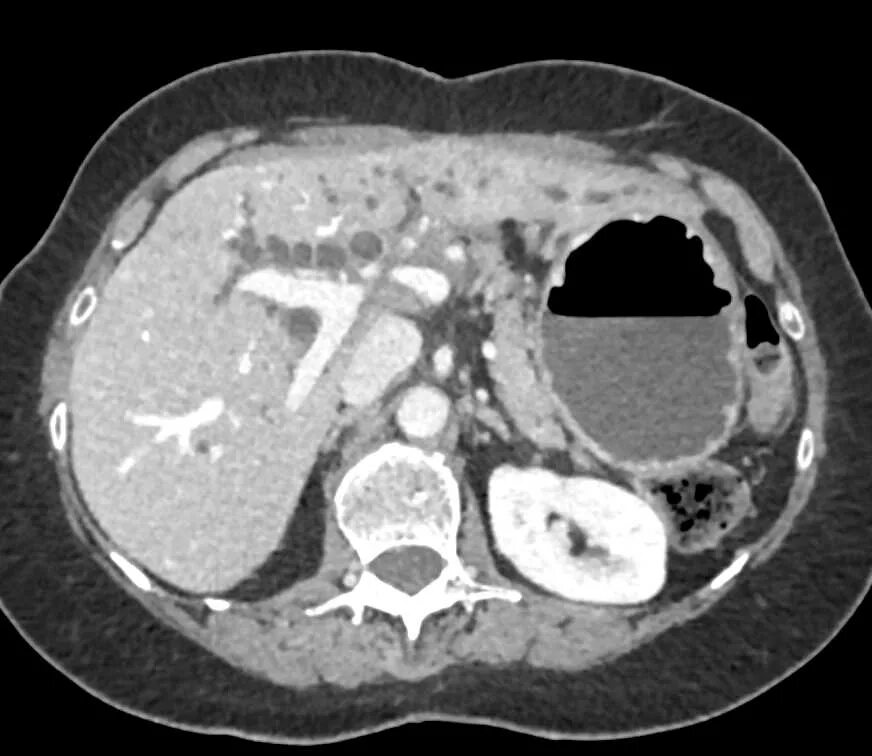

Уплотнение внутрипеченочных протоков